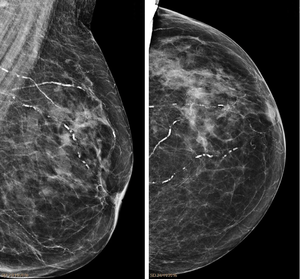

Right breast mammograms showing several calcified arterioles. Patient 94 years old. | |